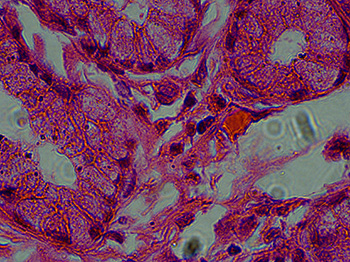

Microscope Image Comparison: ZEISS Primostar versus Motic Panthera

Recently, we looked at images on two different microscope systems: the ZEISS Primostar 3 and the Motic Panthera. We wanted to compare the images captured with both of these microscopes.

For both microscopes, the same digital camera was used to capture the images, a 5 megapixel microscope camera (the DCM5.3). Images displayed were captured with a 100x objective lens. For the ZEISS Primostar 3, the Zeiss iPlan Achromat 100x Objective was used. The Motic UC Plan Achromat 100x objective lens was used on the Motic Panthera microscope.

We found that the images taken with the ZEISS Primostar 3 and the Motic Panthera microscopes were comparable, and you can see for yourself in the table below.